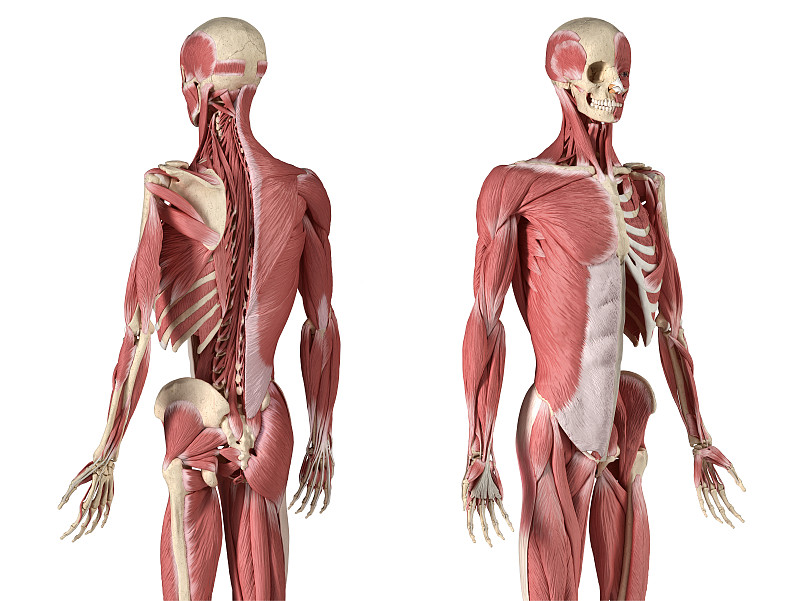

上肢详情